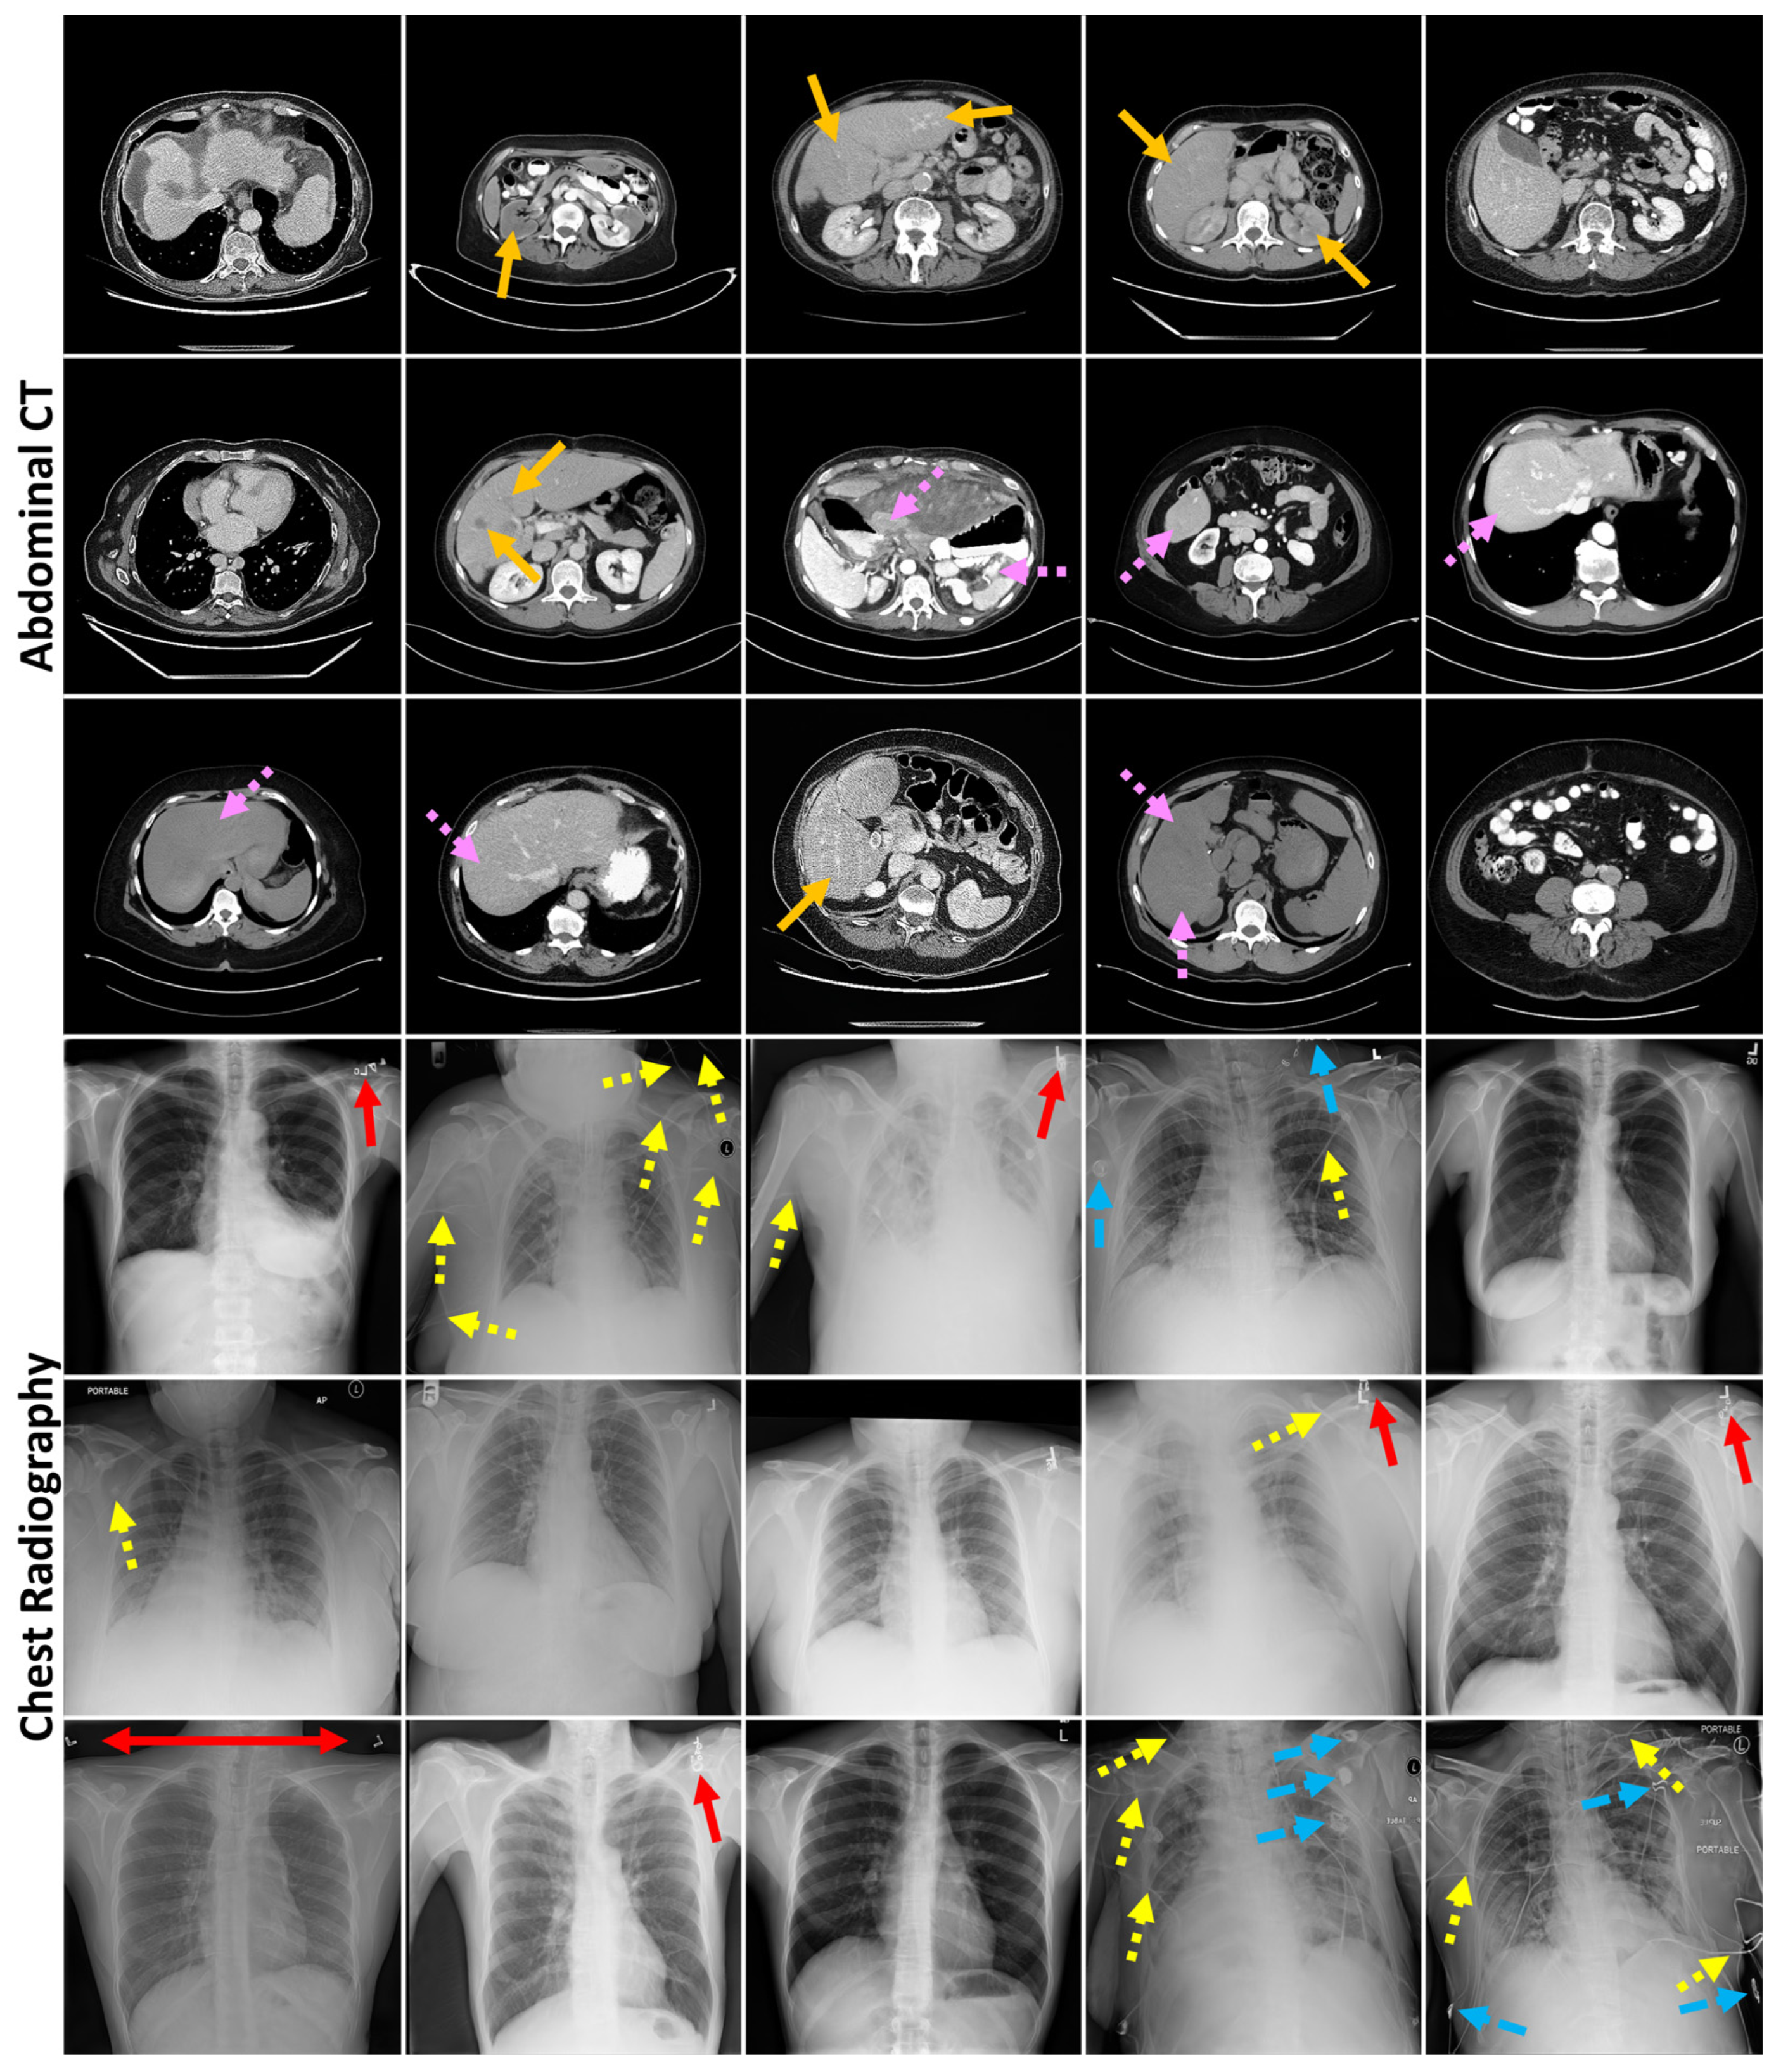

2.1.1. Failure Detection Datasets

2.1.2. Data Curation Datasets

3.4. Localization of Anomalous Regions